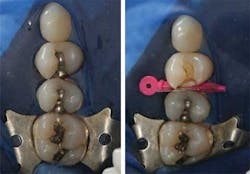

Unlike other low shrinkage posterior restorative materials, the SonicFill restorative system requires no unique bonding agents and can be used with any total-etch or self-etch adhesive system. Due to the unique design of the composite resin and flowable qualities created by the sonic vibration delivered by the handpiece, the restorations can be bulk filled (up to 5 mm) quickly with no voids.

After the handpiece is removed from the cavity preparation, the handling consistency of the composite resin quickly returns to its normal viscous state for easy sculpting and anatomy creation. The small diameter orifice of the SonicFill compules (1.5 mm, compared to conventional ampules of 2.5 mm), coupled with the flowable characteristics of the sonically activated resin, allows for easy placement in even the most conservative clinical preparations.

While conventional layering techniques have proven to be effective, they can lead to voids and require extended placement time, which can increase the likelihood of contamination. During the pilot study, 44 SonicFill restorations were placed.

The average time to volumetrically fill each restoration with the composite material was 40 seconds. The fastest recorded placement time was eight seconds. This represents a fraction of the time generally required by practitioners to place posterior composite restorations using a traditional 2 mm layering technique.

In addition to the time saved by bulk filling, further efficiency is gained by the lack of instrumentation needed to adapt the resin to the walls of the preparation.

The sonic energy that is applied allows the resin to flow through the orifice and adapt to the preparation’s anatomical configuration without spending too much time on material manipulation.